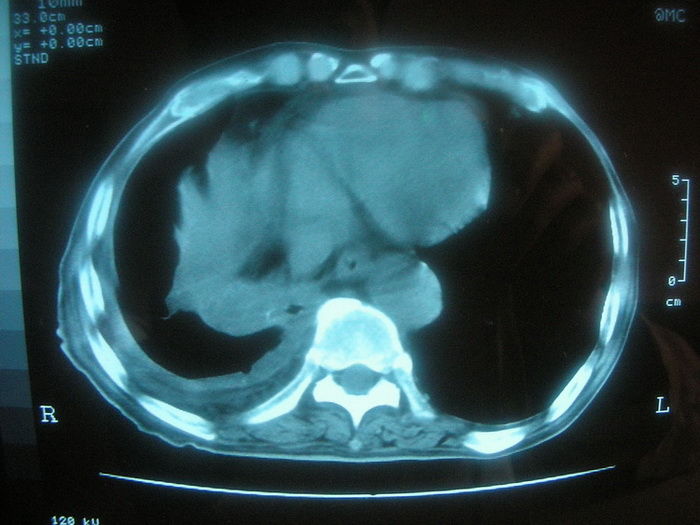

以下是引用卜一在2008-2-16 6:10:00的发言:[br]右肾增大,实质内明显见占位性病灶,并突出体外,密度不均匀。另双肺上叶见散在的斑片 索条及点状结节样致密影,右下肺门区不规则团块,右侧胸腔积液并形成局限性气胸。考虑:1 右肾癌。2 右肺门淋巴结转移及肺内 胸膜转移。3 右上肺陈旧结核。